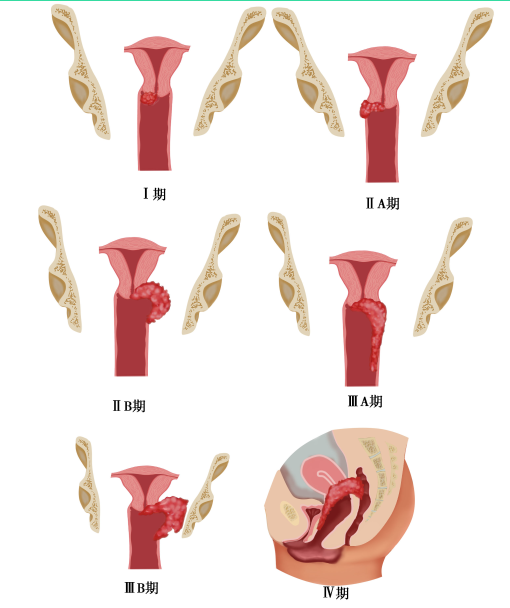

【临床分期】

采用国际妇产科联盟(FIGO,2018年)的临床分期标准(表25-1)。临床分期在治疗前进行,治疗后不再更改(图25-6)。

表25-1 子宫颈癌临床分期(FIGO,2018年)

图25-6 子宫颈癌临床分期示意图